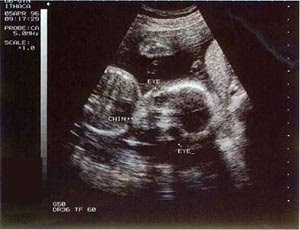

..:[ my baby : 22th week ]:..

A good outline of the face

The baby is getting bigger and continuing to practice for extrauterine life. This week your baby has developed eyebrows! S/he weighs about 15 ounces (425 grams) and is 27.5 cms or 10.8 inches total length!

dis is how my baby looked like.. :)